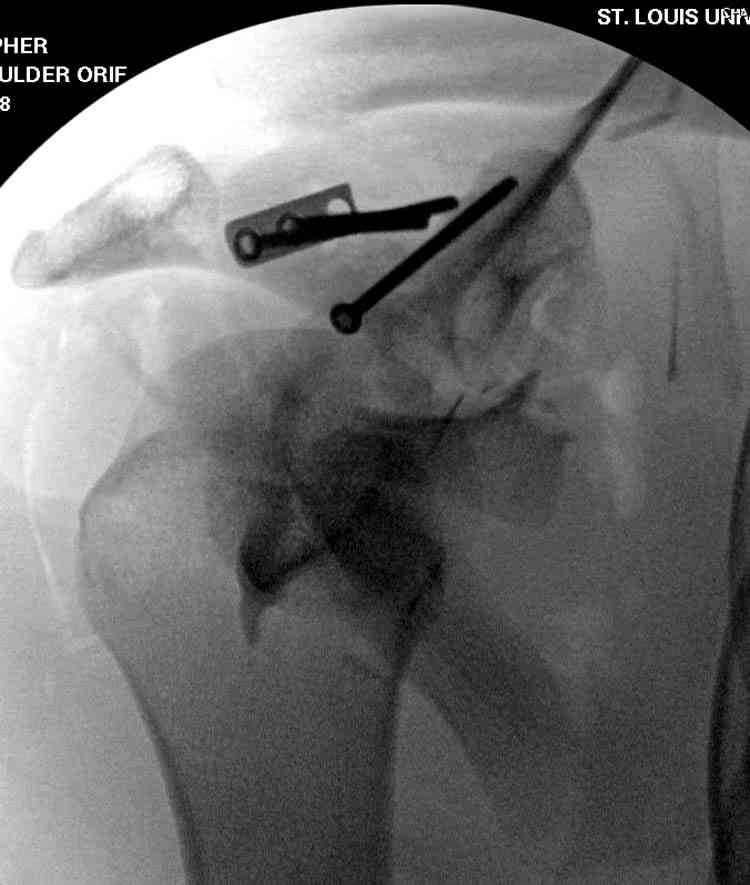

Двумя шурупами сзади на пластине (вместе шайбы)

провели удержание репозиции, а фиксацию провели

следующим косым шурупом.

Последующие этапы на снимках.